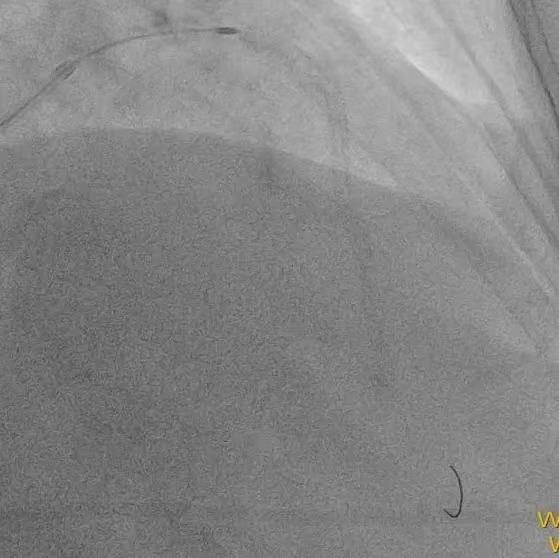

患者74岁,10年前因胸痛诊断为冠心病,在外院放过支架,但当时医生即明确告知家属,血管最严重的“总开关”左主干的地方钙化分叉,处理起来太危险,只是把难度相对不高的血管放了支架。近年来患者间断胸闷、胸痛,伴有心衰下肢肿胀,辗转来我院。冠脉CT显示冠脉严重钙化,因此安排冠脉造影检查。 ![]() ![]() 术前CTA提示左右冠支架术后且左主干重度钙化 (主干没有支架) 冠脉造影

![]() ![]() ![]() 左右冠脉造影:右冠脉支架远段已完全闭塞,旋支远端完全闭塞,前降支中远段重度狭窄,左主干重度钙化分叉。 手术策略